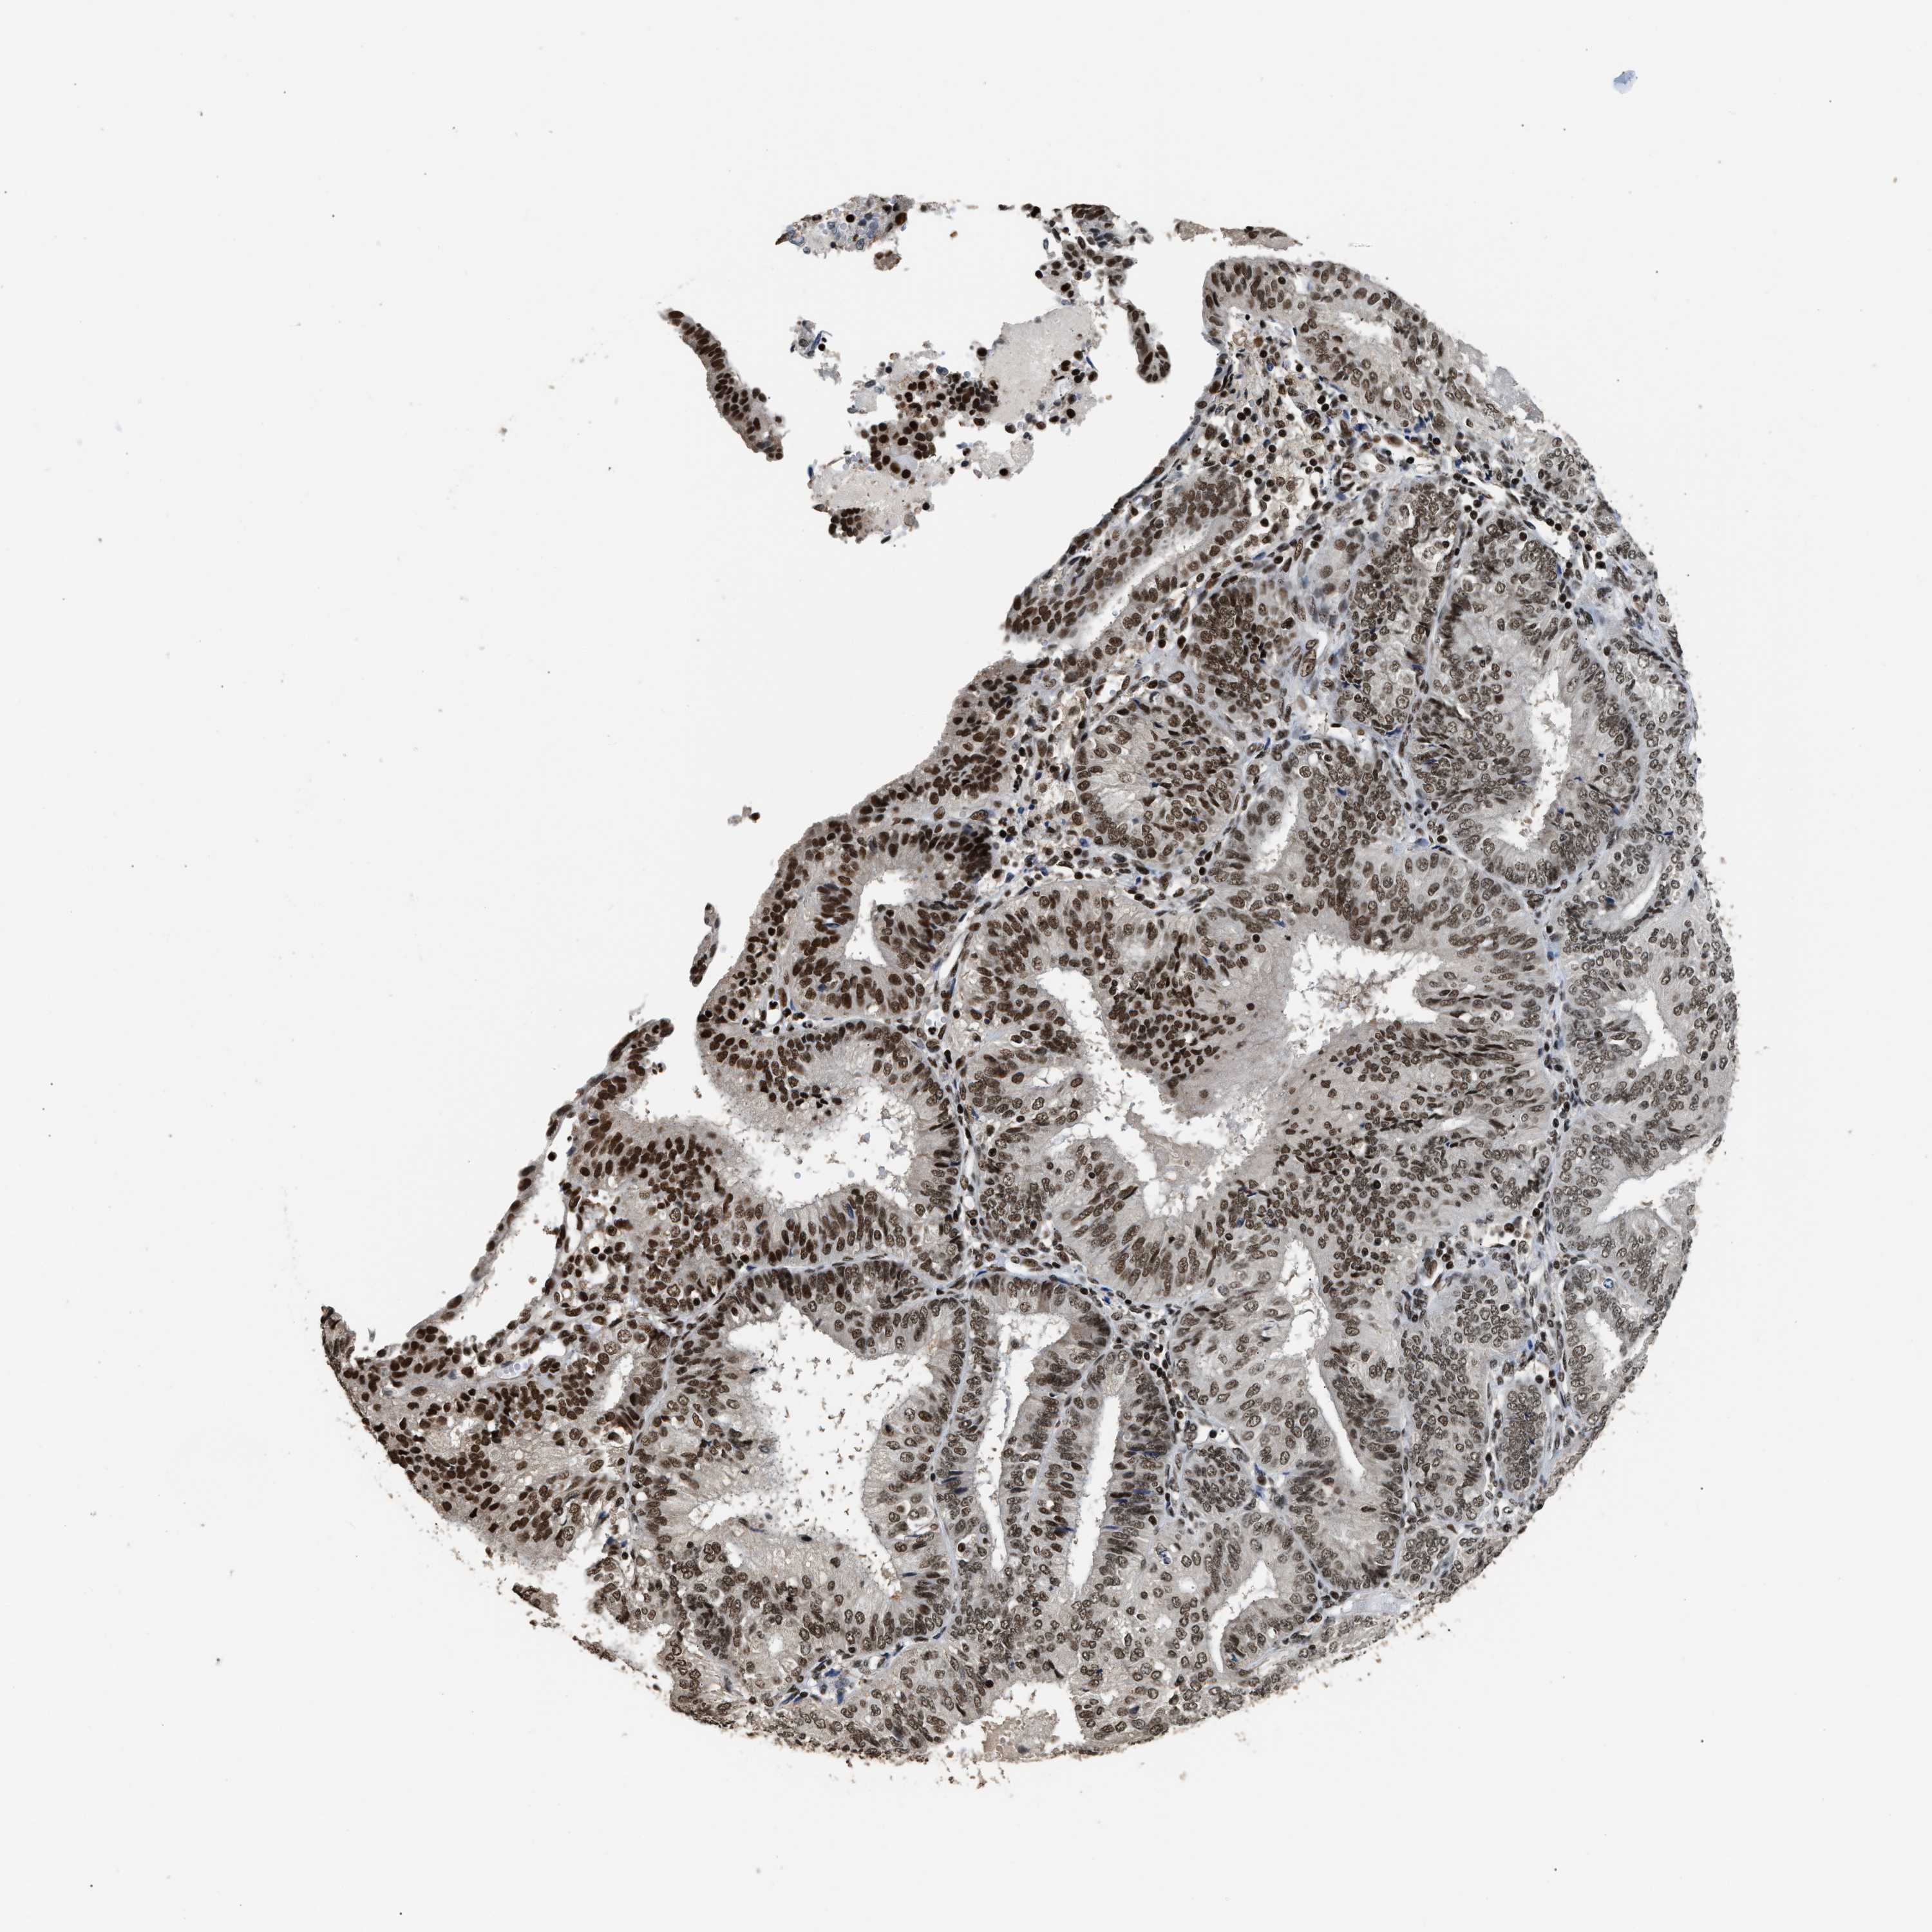

ENDOMETRIAL CANCER - Protein expressioni

A mouse-over function shows sample information and annotation data. Click on an image to view it in a full screen mode. Samples can be filtered based on level of antibody staining by selecting one or several of the following categories: high, medium, low and not detected. The assay and annotation is described here.

Note that samples used for immunohistochemistry by the Human Protein Atlas do not correspond to samples in the TCGA dataset.

Antibody stainingi

Antibody staining in the annotated cell types in the current human tissue is reported as not detected, low, medium, or high, based on conventional immunohistochemistry profiling in selected tissues. This score is based on the combination of the staining intensity and fraction of stained cells.

Each image is clickable and will lead to virtual microscopy that enables deeper exploration of all samples and also displays staining intensity scores, fraction scores and subcellular localization as well as patient and tissue information for each sample.

Antibody HPA020044

Antibody CAB022065

Staining

High

Medium

Low

Not detected

Intensity

Strong

Moderate

Weak

Negative

Quantity

>75%

75%-25%

<25%

None

Location

Nuclear

Cytoplasmic/membranous

Cytoplasmic/membranous,nuclear

Adenocarcinoma, NOS

Adenoma, NOS